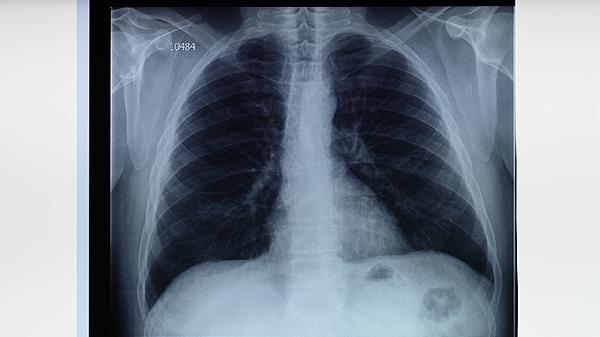

肺结核患者除规范用药外,需保证充足营养摄入,每日摄取足量优质蛋白和维生素。适当进行有氧运动有助于改善肺功能,但要避免过度劳累。保持居住环境通风良好,咳嗽时注意掩住口鼻。严格遵医嘱完成6-9个月全程治疗,即使症状消失也不可擅自停药。定期复查胸部影像学和痰菌检查,密切监测药物不良反应,出现视力模糊、持续发热或黄疸等症状应及时就医。